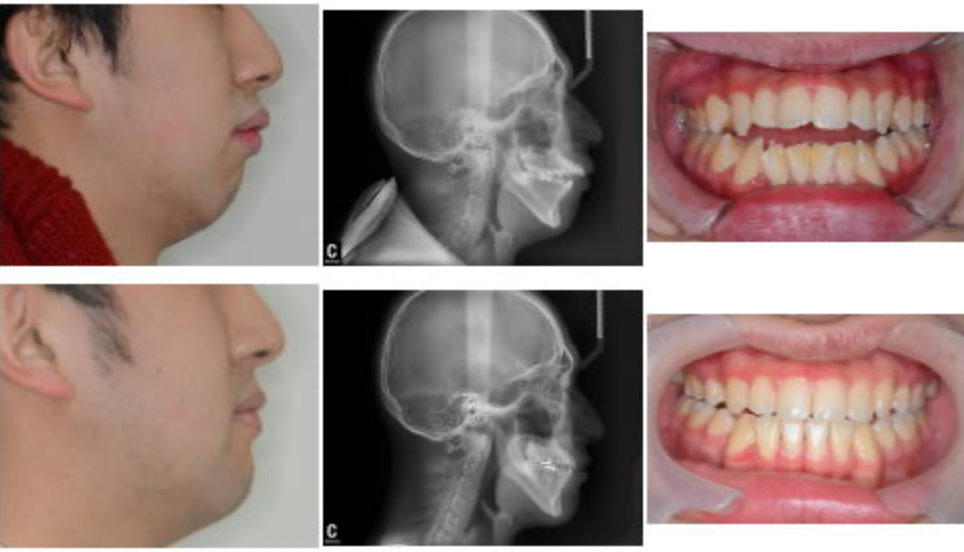

顎がガクガクする、前歯が出ている、ガタガタしているなどの症状でご来院した患者様の症例です。

当クリニックにて、患者様ご自身が心地よいと感じる顎の位置を探し、その位置できちんと咬合できるような噛み合わせに仕上げました。治療期間は長くかかりましたが、安定した咬合と横顔、気道が広がりいびきの改善にも繋がりました。

こちらの患者様の治療には、マルチブラケット矯正装置を使用しています。